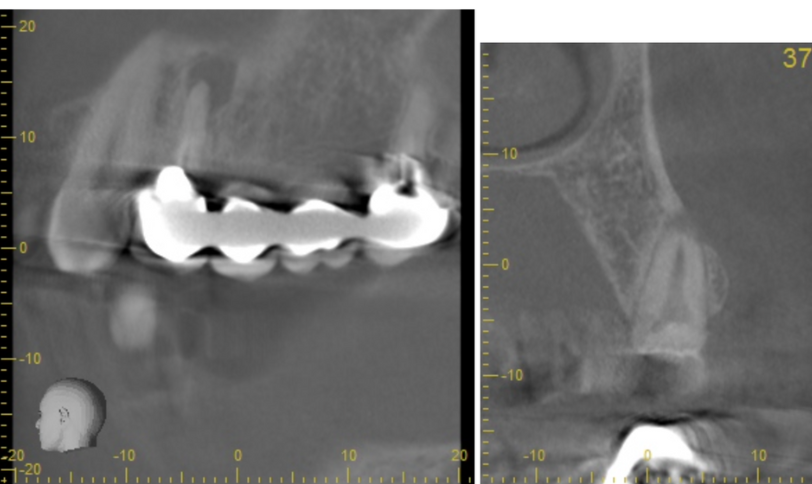

顎堤の吸収がなくインプラントを行うにあたり十分な骨が得られた

| 診断 | ①下顎両側臼歯欠損 ②上顎左側5根尖性歯周炎 ③上顎左側6欠損 ④上顎右側4歯根破折 ⑤上顎右側567欠損 ⑥上顎左側7う蝕 ⑦上顎右側7う蝕 |

| 処置内容 (または主訴) | ①義歯 ②顕微鏡を用いた感染根管治療 ③インプラント治療 ④抜歯→骨造成→インプラント ⑤インプラント治療 ⑥セラミックによる被せ物の修復 ⑦セラミックによる被せ物の修復 |